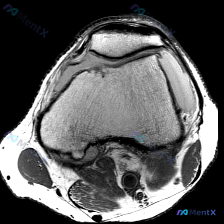

刚看到一份膝关节MRI的软骨异常病例,整理了一下完整的分析思路和大家分享。 一、影像学基本发现 这份病例提供的是膝关节MRI轴位影像,核心观察结果如下: 1. 髌股关节:关节间隙清晰,但髌骨外侧关节面和对应股骨滑车外侧面的软骨存在信号不连续、变薄、表面毛糙,髌骨软骨下骨表面信号不均匀、轮廓改变,提示...